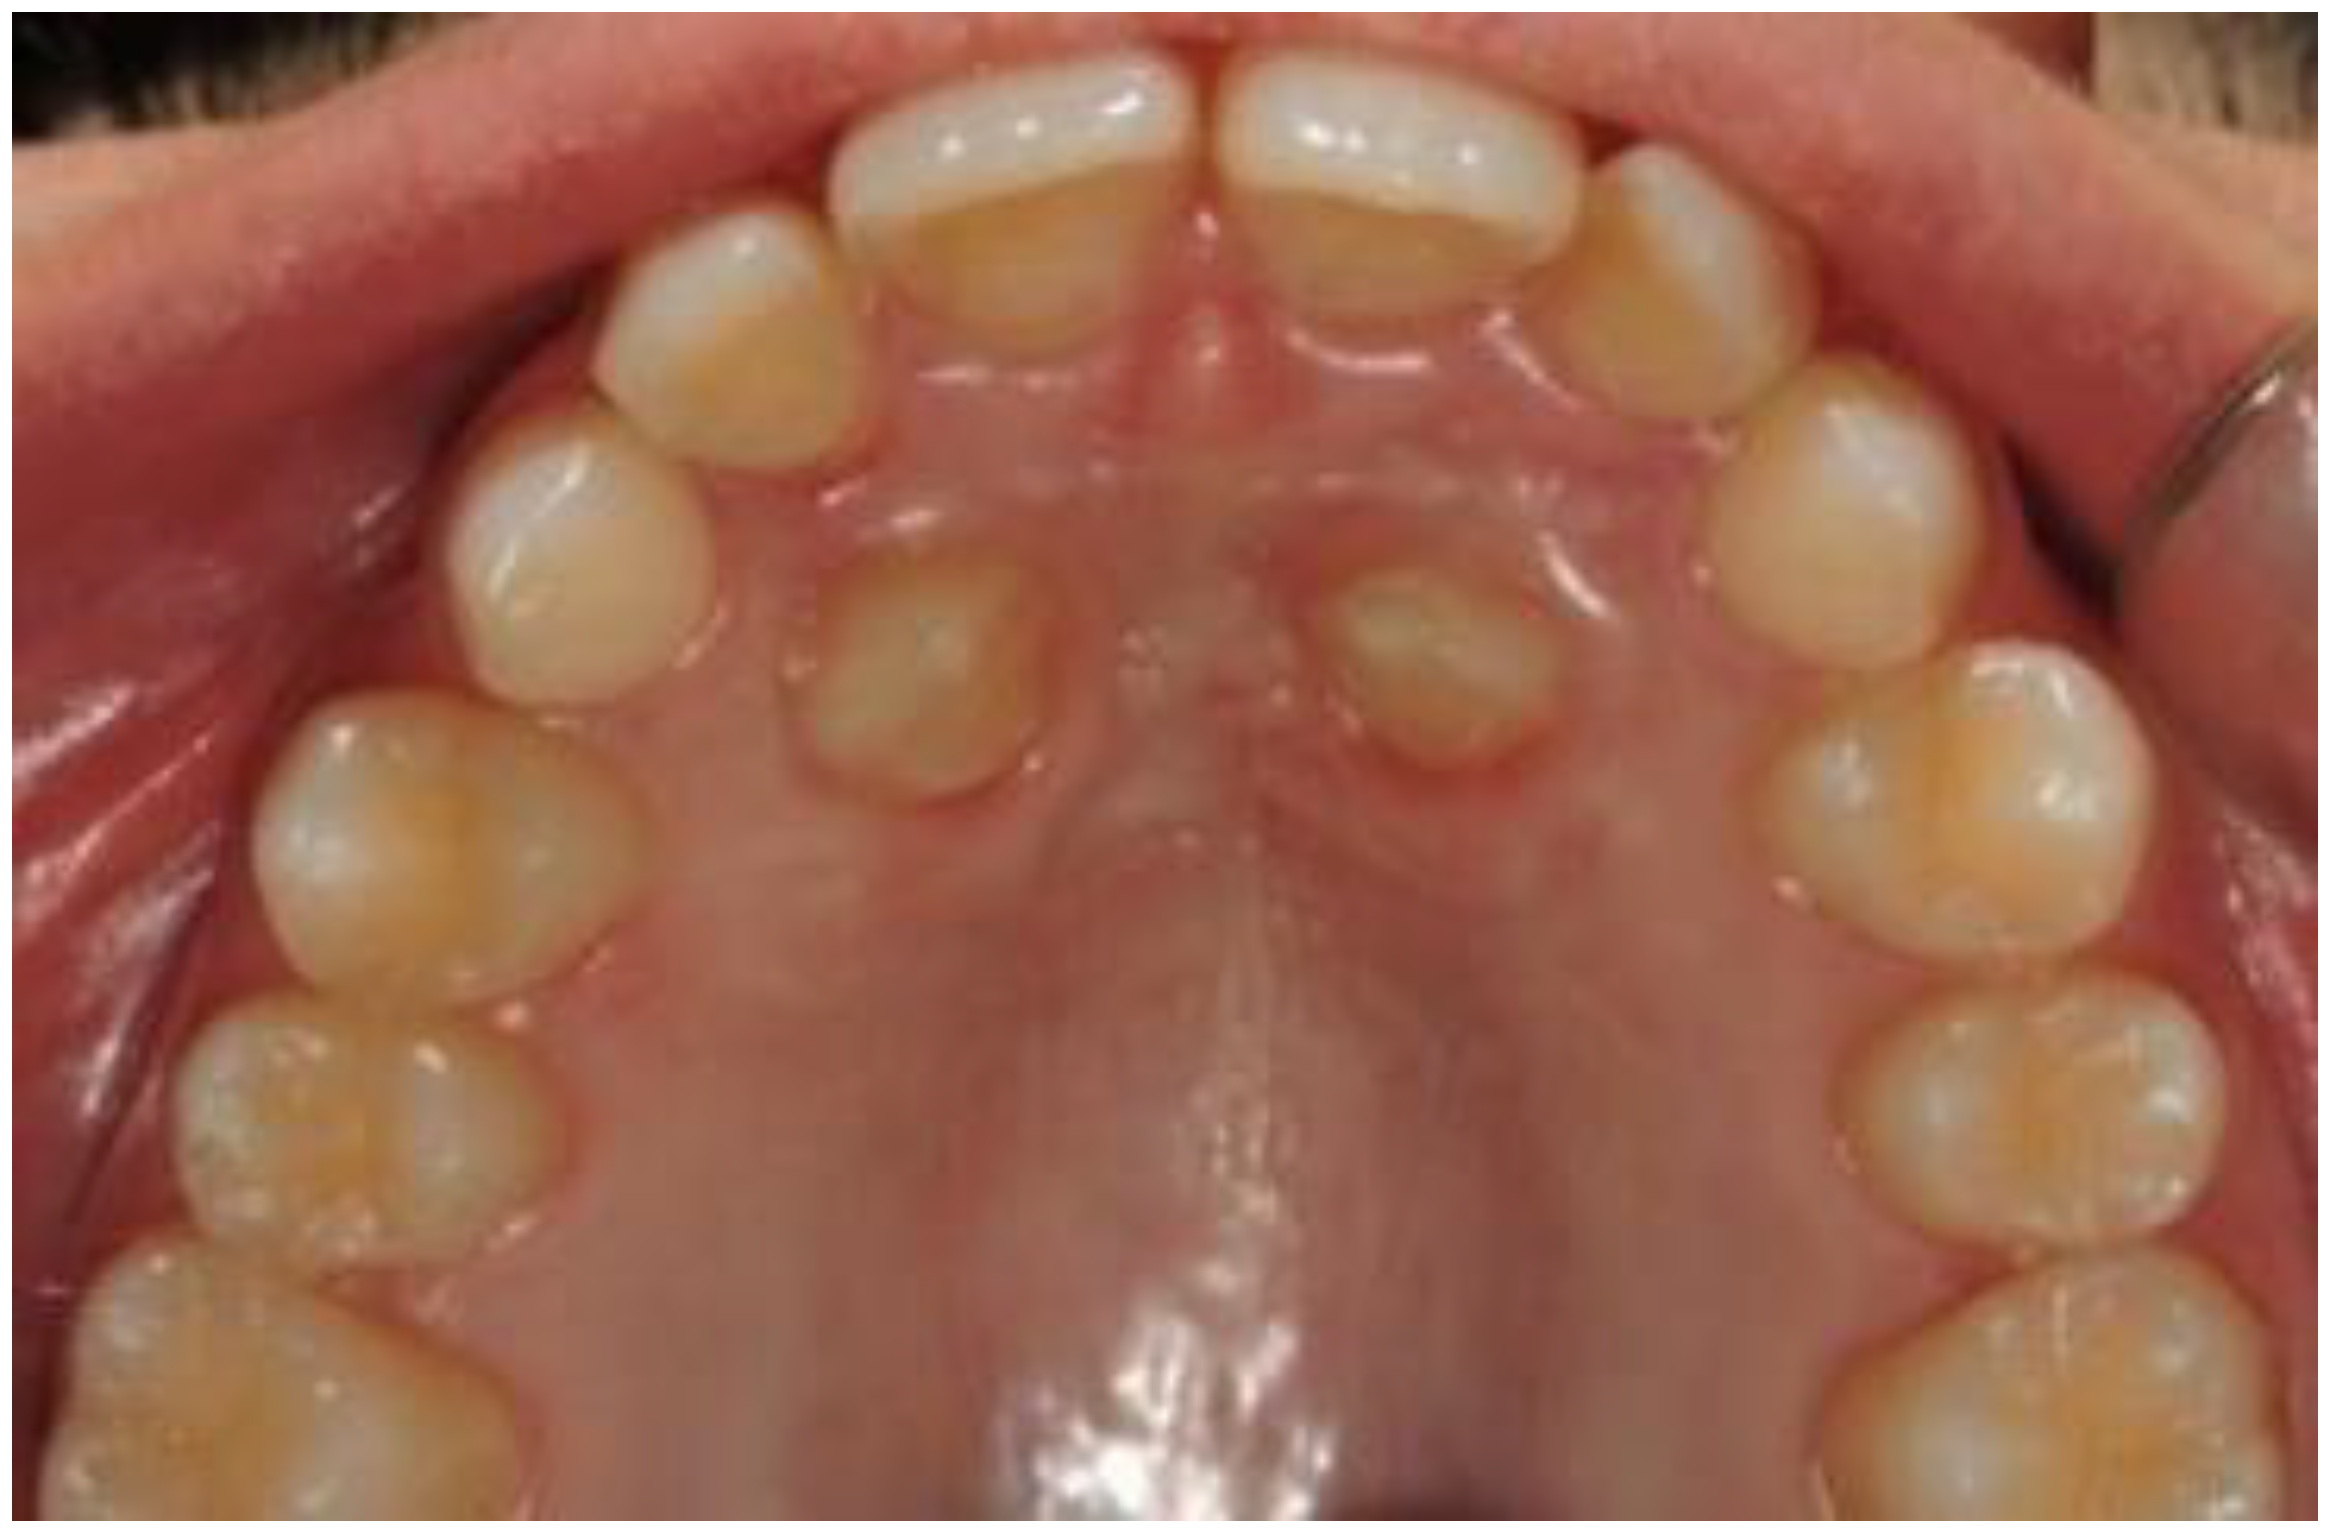

2. Case Presentation